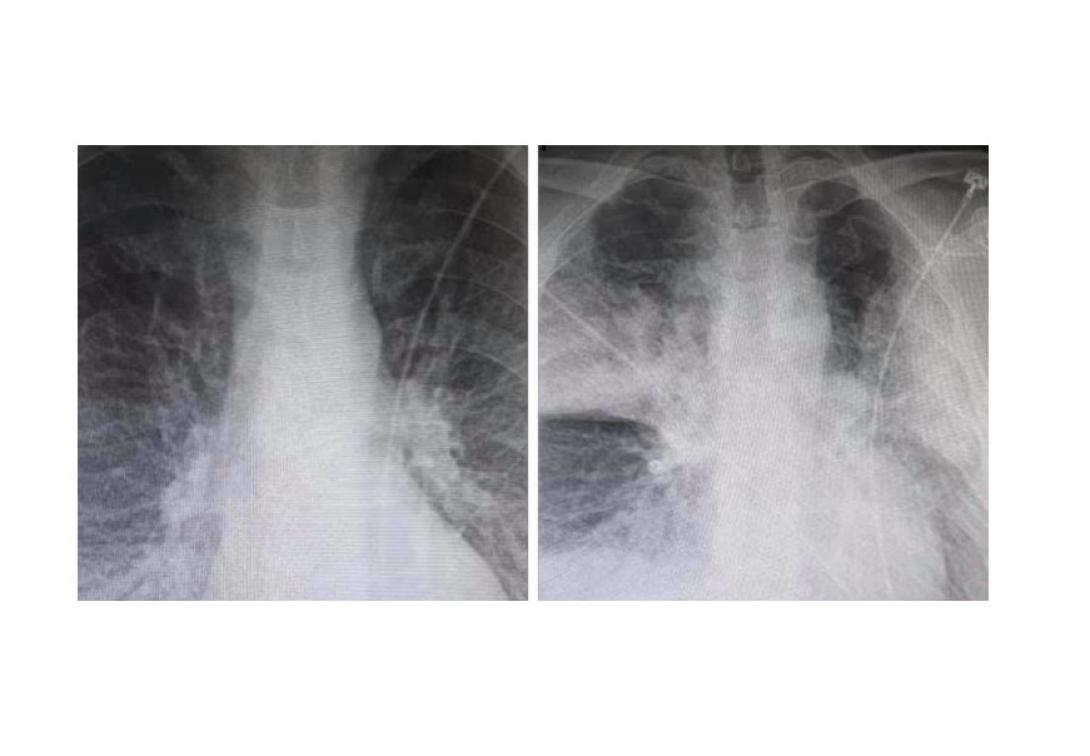

Παλιές οι ακτινογραφίες του "ασθενή με κορωνοϊό";

Του 2015 φαίνεται πως ήταν οι ακτινογραφίες που δόθηκαν στη δημοσιότητα από γιατρό του ΚΑΤ, υποστηρίζοντας ότι παρουσιάζουν την επιβάρυνση της υγείας ασθενή με κορωνοϊό μέσα σε μικρό χρονικό διάστημα.